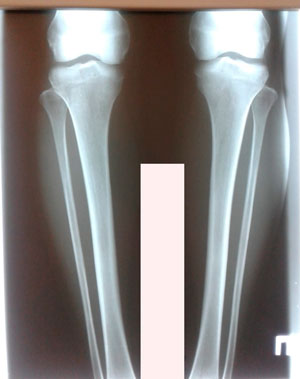

Исходник - 33 года.

Дата операции - 04.10.2019г.

IMG_6247-05-10-19-08-04.JPG

IMG_6249-05-10-19-08-04.JPG